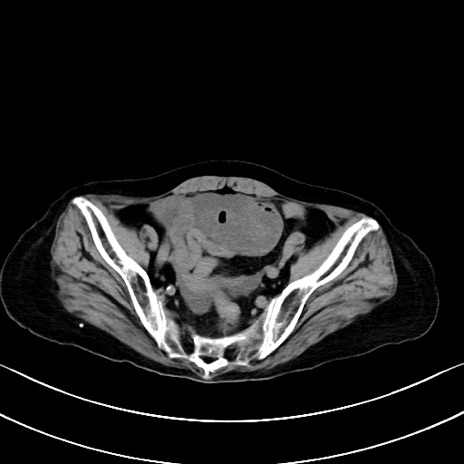

横断像

他院CT